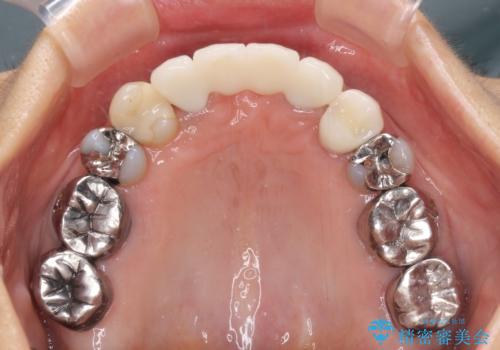

話しにくく腫れやすい前歯のブリッジ 使用感の良いオールセラミックブリッジに

- 矯正治療を行った歯科医院で装着した前歯の仮歯が不快とのことで来院された患者様です。

仮歯自体はとても綺麗でしたが、2本の歯が欠損している部分に上唇小帯が入り込んでいたため、歯肉形成を行った上で仮歯を調整し、オールセラミックブリッジを装着することとしました。

上唇小帯を切除したことで、ブリッジのダミー部分に触れて腫れていた歯肉は健全な状態になりました。

隙間もなくなったことで話す際の空気の漏れや、ものが挟まることもなくなりました。